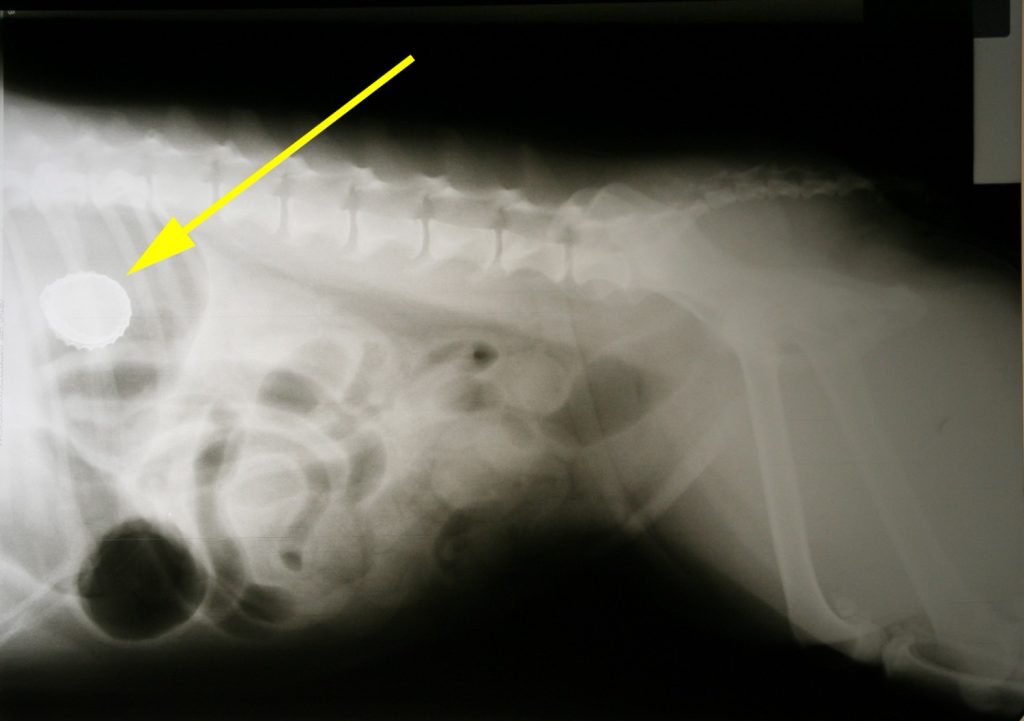

Bij het algemeen lichamelijk onderzoek viel met name op dat de temperatuur 40 graden was, de buik voorin een beetje gevoelig was en er iets bloed aan de thermometer zat. Het leek allemaal mee te vallen maar toch zat ze ons op de een of andere manier niet lekker. In overleg hebben we besloten een rontgenfoto te maken van de buik. Hierop zagen we al snel het probleem: in de maag zat een prachtig voorbeeld van een kroonkurk.